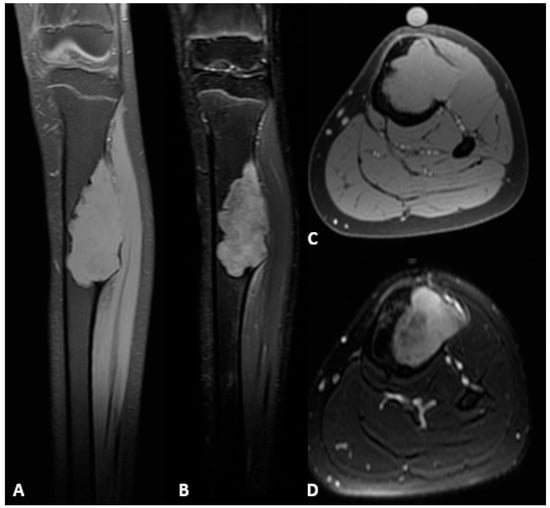

- Fixation of the transport segment: A locking bolt was inserted into the transport segment to engage the internal transport mechanism of the intramedullary nail (Figure 5).

Figure 5. Intraoperative anteroposterior radiograph showing the locking bolt inserted into the transport segment. (1) Proximal tibial diaphysis and transport segment. (2) Intramedullary nail. (3) Intact fibular diaphysis. (4) Locking bolt within the transport segment and internal motor of the intramedullary nail. (5) Distal tibia, osteotomy of the transport segment. - Nail locking: The nail was locked proximally and distally to achieve stable fixation.